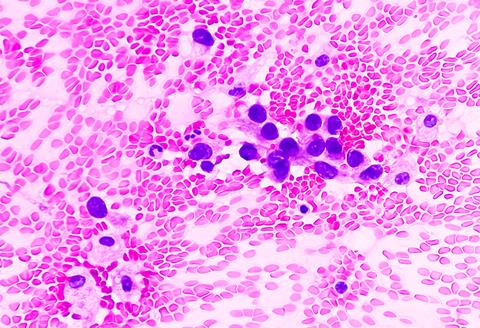

He added: “Patients, physicians, and researchers know they can rely on this predictive modelling because it is self-taught, provides explainable decisions, and is based only on the knowledge drawn specifically from each patient’s tissue, including such features as its proportion of dying cells, tumour-fighting immune cells, and how densely packed the tumour cells are, among other features.”

The researchers first analysed lung adenocarcinoma tissue slides from the Cancer Genome Atlas to develop the HPL algorithm. Lung adenocarcinoma is histologically heterogeneous, with five distinct histologic growth patterns: bronchioloalveolar (lepidic), acinar, papillary, micropapillary, and solid.1 Having these characteristic features was the reason why this disease was chosen to develop the algorithm.

Tumour recurrence was associated with characteristics including high tile percentages of dead cancer cells and lymphocytes, as well as tumour cells in the lungs’ outer linings. An increased likelihood of survival was associated with high percentages of unchanged or preserved lung sac tissue, and lack of or small presence of inflammatory cells.